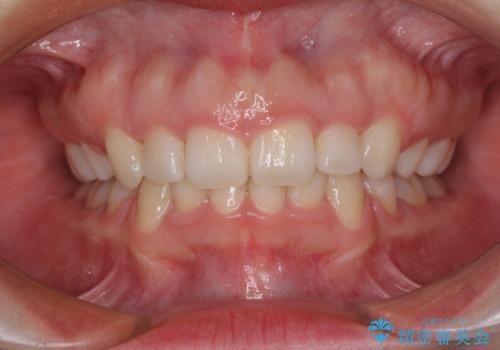

- 抜歯した歯や抜歯が必要と思われる歯を放置したため、奥歯に不快を感じているとのことで来院された患者様です。

右下は奥歯が抜歯したスペースを塞いでしまい、左下はブリッジの支台歯の1つが破折している状態でした。

また、下顎前歯にはスペースがあり、コンポジットレジンでスペースを閉じている状態だったので、前歯のスペースを解消しつつ、奥歯にスペースを獲得するよう矯正治療を行うこととしました。